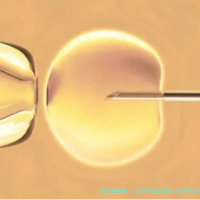

PGS技术的原理:PGS即是胚胎植入前遗传学检查筛选,是在胚胎移植前,对初期胚胎进行染色体量数和结构异样的检测。通过对胚胎的染色体进行分析,评价胚胎是否是存留染色体非整倍体等等问题,从而筛选出染色体正常的健康胚胎进行移植。

筛选过程:起首,在试管婴儿治疗过程当中,通过促排卵取得多个卵子,与精子结合组成受孕卵并培养至囊胚阶段。然后,医生会从囊胚从中获取出数个细胞个体进行检测。这一过程须要在专业的实验室中由有经验的医生操作,以保障不影响胚胎的发育。接下来,实验室利用前沿的基因检测技术,如新一代测序技术(NGS)等,对拿出的细胞个体进行染色体解析。最后,根据检测结果,选择染色体正常的胚胎进行移植,这般可以大大降低早产和胎儿染色体异常的风险。